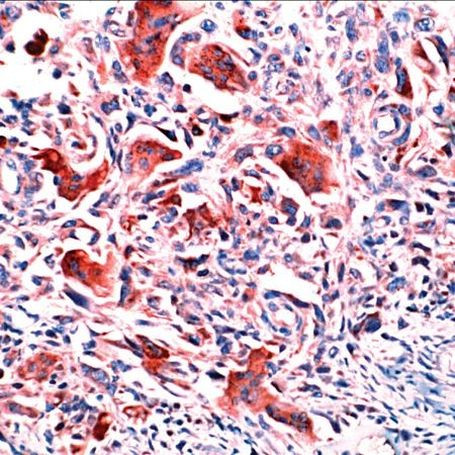

Osteopontin Polyclonal Antibody

Heat-mediated antigen retrieval is recommended prior to staining, using a 10mM citrate buffer, pH 6.0, for 10 minutes followed by cooling at room temperature for 20 min. Following antigen retrieval, incubate samples with primary antibody for 10 min at room temperature. A suggested positive control is breast carcinoma.